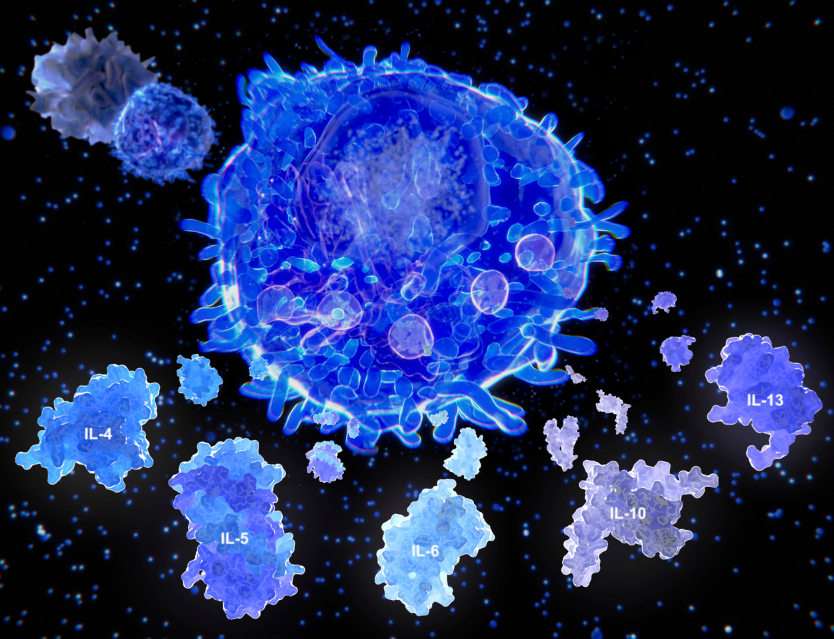

LA CONEXIÓN ENTRE LOS TEJIDO PERMITE EL EFECTO DEL VENDAJE NEUROMUSCULAR

PIEL / FASCIA / MÚSCULO

La FASCIA SUPERFICIAL se une a la piel y a la FASCIA PROFUNDA a través de unas fibrillas diagonales y perpendiculares rodeadas de tejido graso en su mayoría. Y a su vez, la fascia muscular profunda se une al músculo a través del epimisio (capa de tejido conjuntivo que rodea al músculo).

Este mecanismo se produce gracias a la conexión entre los tejidos y a la propiedad elástica del vendaje neuromuscular, el cual genera una tracción y transmisión de dicha tracción desde la primera capa de la piel hasta la fascia profunda, epimisio y músculo. Esta tracción transmitida generará la activación de receptores locales y activación del mecanismo reflejo de defensa que intentarán mantener el estado de reposo, obligando a las capas profundas a moverse en el mismo sentido de la tracción que genera el vendaje neuromuscular.

Dicho de otro modo, la capa superficial de la piel se mantiene en estiramiento constante por la tracción del VENDAJE NEUROMUSCULAR y para conseguir una posición de reposo, la capa profunda, debe deslizarse en la misma dirección. El organismo buscará la relajación de las fibras que conectan las diferentes capas.

Hay que tener en cuenta que el tejido subcutáneo o fascia superficial comparte inervación con el músculo en la zona que limitan ambos con la fascia profunda, así que cuando se provoca un estímulo de deslizamiento entre el tejido subcutáneo y la fascia, estaremos provocando un estímulo sobre el músculo para contraerse o relajarse.